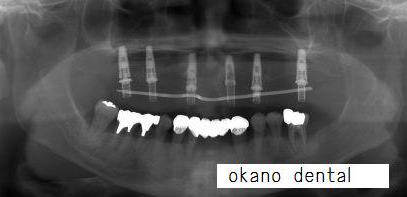

| @上顎総入れ歯からインプラントブリッジ(ノーベルバイオケア使用症例) | |||||||||||||||||||||||||||||||||||

| このように上には、壊れた根が1本あるだけの総入れ歯をされていました。 | |||||||||||||||||||||||||||||||||||

| ハーバード大学では、Dr.Galluciが上下無歯顎の場合、下顎では6本、上顎では8本のインプラントを推奨していました。 ハーバード大学では、ストローマンインプラントを使用しています。 |